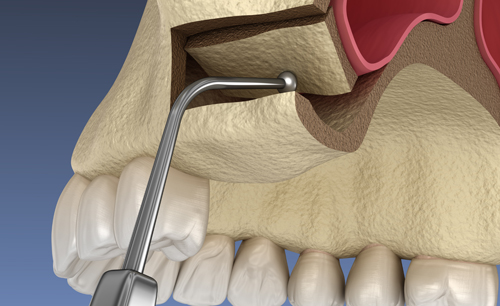

infografía explicativa de elevación de senos

infografía explicativa de implante con elevación de seno

En la Clínica Dental ECCO aplicamos técnicas quirúrgicas de regeneración ósea previa a la colocación de los implantes: injertos óseos, obtención de plasma rico en factores de crecimiento, preservación alveolar y elevación de senos maxilares.